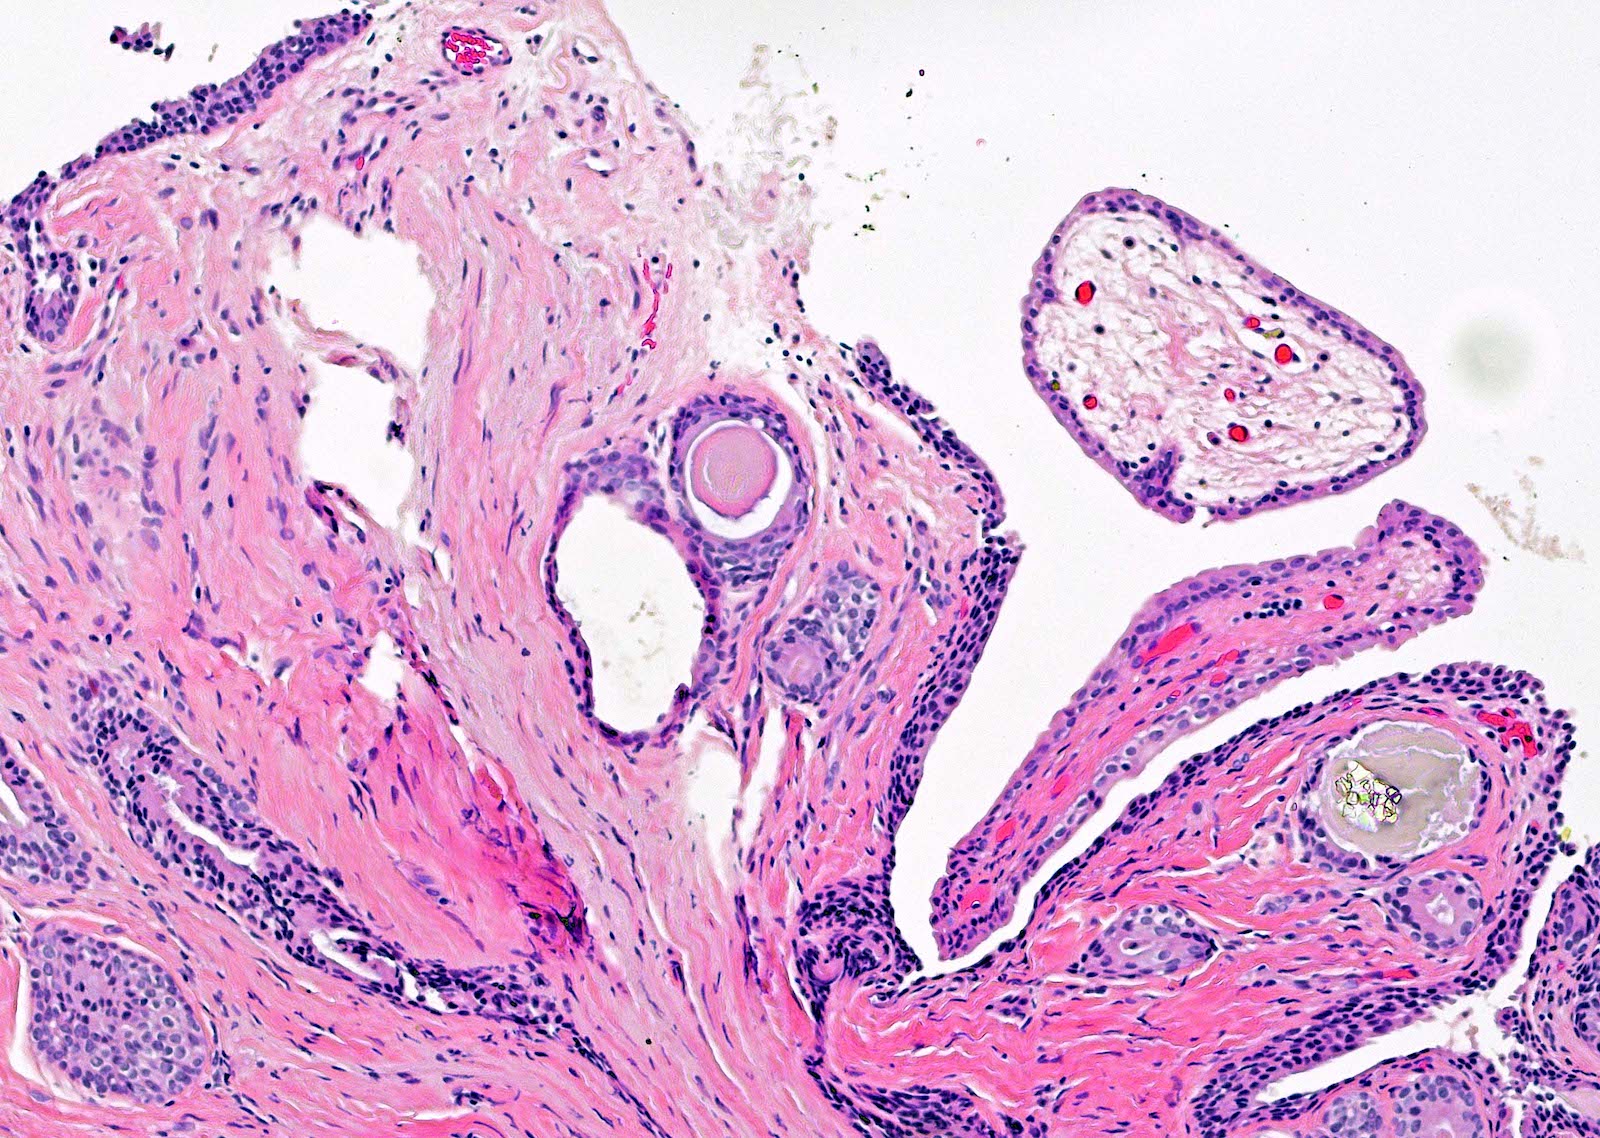

- Fibroepithelial urethral polyp (Am J Surg Pathol 2005;29:460):

- Pattern 1: most common pattern includes the following features

- Broad cloverleaf-like and club-like projections covered by normal urothelium and composed of dense fibrovascular stroma with florid cytitis cystica et glandularis (most common morphologic variant)

- Back to back glands present in the stalk

- Anastomosing nests of benign urothelial cells resembling inverted papilloma

- Dilated cysts with intracystic papillary contents

- Degenerative reactive atypia of stromal cells

Microscopic (histologic) images

Contributed by Y. Albert Yeh, M.D., Ph.D.

Fibroepithelial polyp